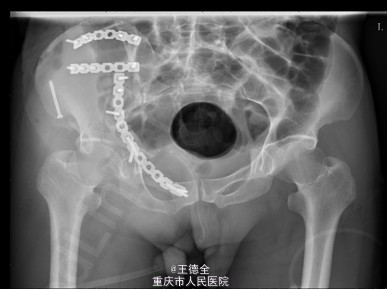

患者男性,51岁,因“高坠伤致左腰部及右髋部疼痛伴活动障碍3天”入院。

查体:急性痛苦面容,神志清楚,平车送入病房,右髋部软组织稍肿胀,局部皮肤完整,未见明显皮疹,挫擦伤及出血点.右股骨髁上骨牵引在位,左腰椎伴明显压痛,骨盆挤压实验阳性,可扪及骨擦音,骨擦感.双下肢感觉,活动,血循良好,足背动脉搏动好;右踝关节主动活动受限,被动活动正常。右侧各足趾背伸、跖屈活动正常,其余各关节活动正常。骨盆X线片示:右侧髂骨、髋臼、双侧耻骨上支、右侧耻骨下支多发骨折,左侧髂骨翼骨折,骨盆出入口右侧份形态失常。辅查影像学资料见下图。

初步诊断:右髋臼粉碎性骨折(Judet X 型) ,诊疗计划:完善双下肢静脉彩超等检查;给予预防深静脉血栓、骨牵引治疗;给予止痛等对症支持治疗;密切观察病情变化,根据病情及时处理。